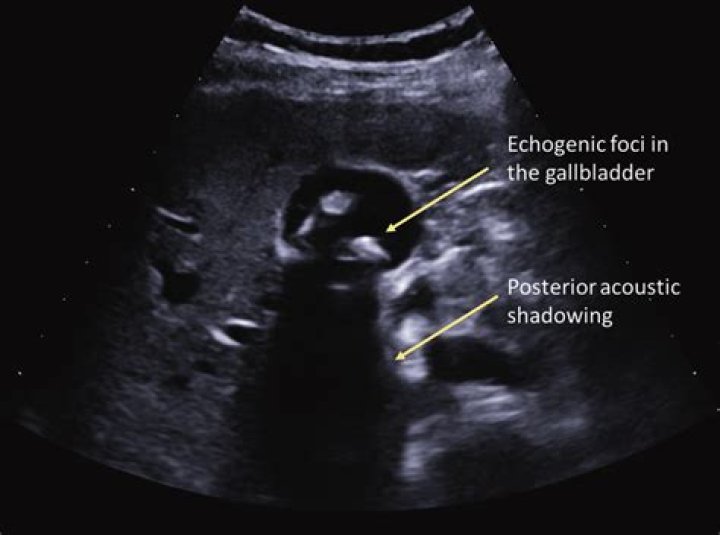

Gallstones appear as echogenic foci in the gallbladder. They move freely with positional changes and cast an acoustic shadow. (See the image below.) Cholecystitis with small stones in the gallbladder neck.

Gallstones on ultrasound have the appearance of hyperechoic structures within the gallbladder with distal acoustic shadowing. Sludge in gallbladder may also be seen, with an appearance of hyperechoic layering within the gallbladder. Sludge, unlike stones, does not cast acoustic shadowing.

What are shadowing gallstones?